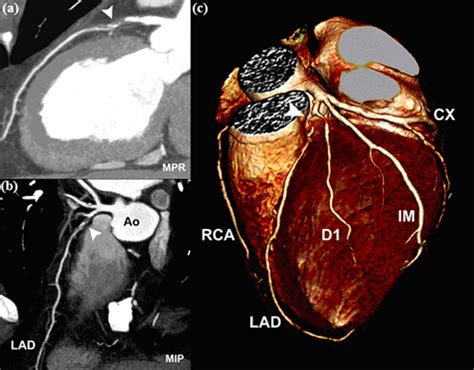

Seguimiento con Resonancia Magnética (RMN)

Tres meses después, se realizó una RMN para evaluar con mayor detalle el estado de las arterias coronarias y el corazón. Los resultados de la RMN proporcionaron información adicional sobre la morfología y función cardíaca.

Imagen de RMN cardíaca